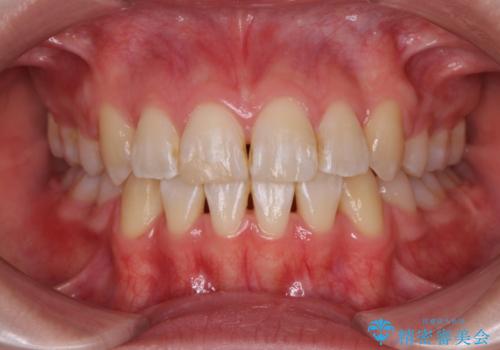

- 前歯を後ろに下げたい ワイヤー矯正(クリア装置)